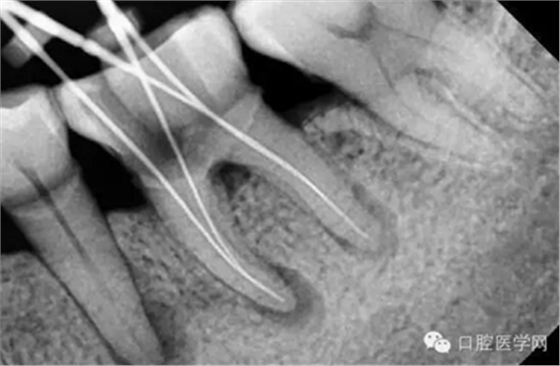

特殊情況可以插針拍片確定工作長度(一般我比較相信根測)

我在臨床中一般用第二中方法較多,手?jǐn)U機(jī)擴(kuò)配合使用,髓開好之后,探查根管,看看有幾個根管,確定根管之后根上三分之一初步疏通,感覺有無阻力,倘若通暢,開始根上三分之一端的預(yù)備,用SX機(jī)擴(kuò),預(yù)備好之后,開始測長度,長度確定好后,S1,S2,F1,F2依次逐步深入法預(yù)備 ,很快就整個預(yù)備結(jié)束,最后再返回來測一次長度,長度準(zhǔn)確,次氯酸鈉反復(fù)沖洗,干燥,準(zhǔn)備試尖根充。